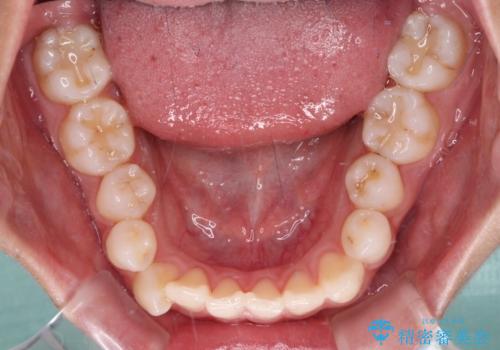

- 前歯のデコボコと奥歯の咬み合わせを気にして来院された患者様です。

右側の奥歯は、上が外側に転位した鋏状咬合を呈しており、前歯のデコボコ改善と並行して咬み合わせを改善していく必要がありました。

装置はワイヤー装置でもインビザラインのマウスピースでもどちらでも適用でしたが、自己管理の煩わしさを嫌い、ワイヤー矯正にて治療を行うこととしました。

ワイヤー矯正を選択されたため、鋏状咬合を確実に改善するために補助装置を併用することとしました。